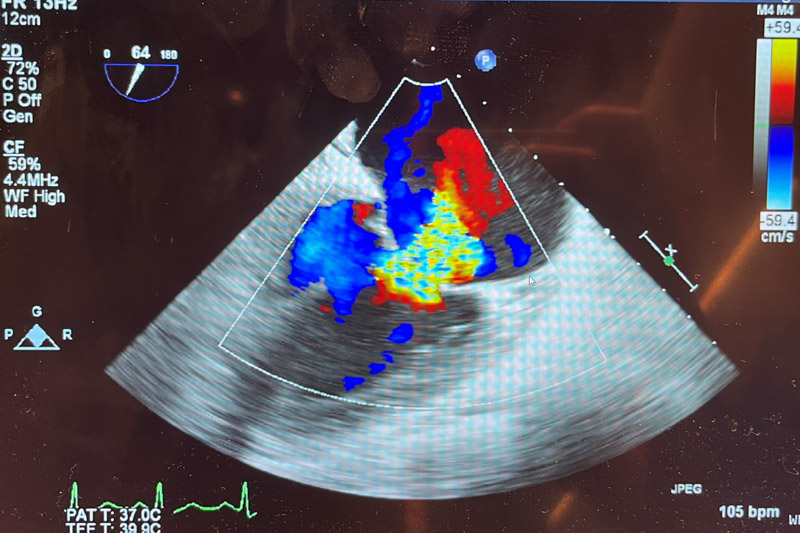

韋阿姨在當(dāng)?shù)刂委熈艘欢螘r(shí)間,癥狀并沒有好轉(zhuǎn),隨后,在柳州工作的兒子陪同她來到柳州市人民醫(yī)院心血管內(nèi)科就診。檢查發(fā)現(xiàn),患者二尖瓣前葉脫垂并重度關(guān)閉不全(反流面積10.7cm2),左室壁運(yùn)動(dòng)普遍減低(EF48%),情況非常嚴(yán)重,救治刻不容緩!

充分完善術(shù)前評(píng)估后,8月19日上午,在阜外醫(yī)院潘湘斌教授及超聲醫(yī)生鄧燕技術(shù)支持下,順利將手術(shù)系統(tǒng)送入患者左心房,到達(dá)二尖瓣A2P2反流處,反復(fù)評(píng)估二尖瓣反流位置、抓捕位置、反流程度,精準(zhǔn)夾合,成功植入1個(gè)二尖瓣夾。術(shù)后患者反流情況明顯改善,跨瓣平均壓差2mmHg,其他各項(xiàng)生理指標(biāo)正常,反流改善明顯,術(shù)前反流4+,術(shù)后反流小于1+,手術(shù)順利完成。